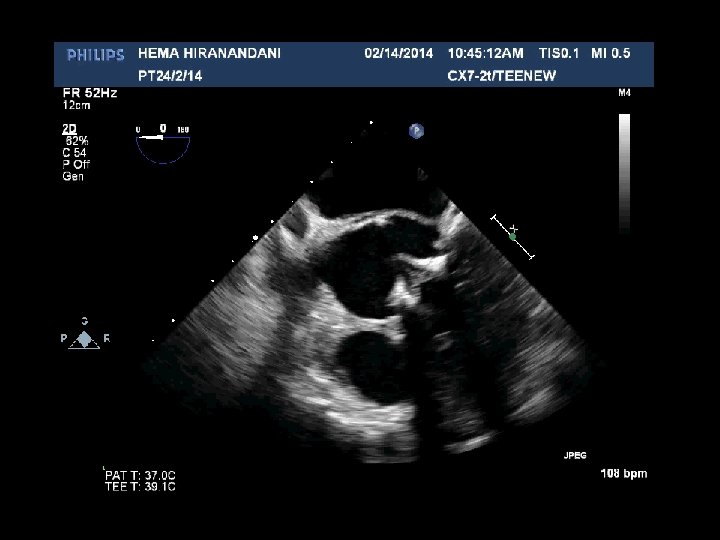

HEMA HIRANANDANI F 57 YRS • • • AVR BIO PROSTHETIC VALVE DEHISCENCE IE MULTIPLE VEGETATIONS ON BIO PRO VALVE AO ROOT ABSCESS SEVERE PARAVALVULAR AR RVSP= 37 mmhg

Hema Hirandani